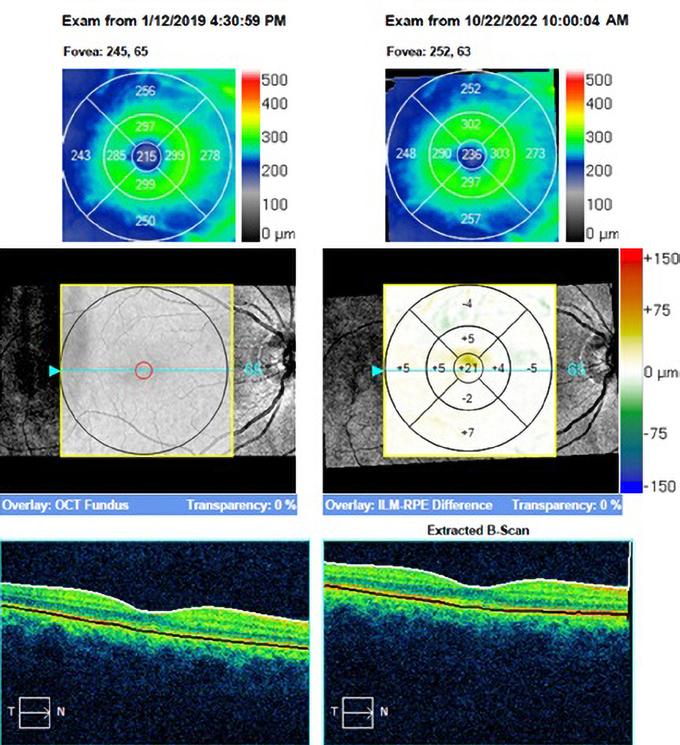

Efectele toxice asupra retinei se manifestă la nivel macular. În timp ce toxicitatea incipientă poate fi asimptomatică, pacienții cu stadii mai avansate de toxicitate pot acuza schimbări în percepția culorilor sau scotoame paracentrale. Toxicitatea avansată la hidroxiclorochină se prezintă sub forma unei maculopatii în formă de țintă. Deoarece toxicitatea retiniană este de obicei ireversibilă, detectarea precoce aacesteia și întreruperea administrării agentului responsabil reprezintă cel mai bun tratament. Toxicitatea corneană se manifestă prin depunerea intraepitelială a medicamentului în cornee, ceea ce afectează rar vederea. Disfuncția corpului ciliar perturbă acomodarea și este rară.

Hidroxiclorochina se leagă de melanină, se acumulează în epiteliul pigmentar retinian (RPE) și rămâne acolo pentru perioade lungi de timp. Ea are toxicitate directă asupra RPE, determinând leziuni celulare și atrofie. Aceasta se întâmplă datorită perturbării metabolismului RPE, în special din cauza leziunilor lisozomale, și a activității de fagocitoză reduse față de segmentele externe ale fotoreceptorilor eliminați. Acumularea segmentelor externe ale fotoreceptorilor duce la degenerescența RPE, migrația în retina externă și în cele din urmă pierderea fotoreceptorilor.

Se recomandă efectuarea unui examen oftalmologic complet înainte de începerea sau în primul an de tratament cu hidroxiclorochină. În cadrul acestui examen, pacienții ar trebui să facă o examinare a fundului de ochi; câmpurile vizuale (fig. 1) și tomografia de coerență optică (fig. 2) ar trebui să fie adăugate în cazul în care există maculopatie. Screeningul anual ar trebui să înceapă după 5 ani de utilizare a medicamentului pentru cei mai mulți pacienți, dar ar trebui să înceapă mai devreme la cei la care există factori de risc majori. Screeningul anual ar

La primele semne de toxicitate retiniană, hidroxiclorochina ar trebui întreruptă pentru a preveni deteriorarea ulterioară a retinei și pierderea vederii. În general,

6 www.revistamedicalmarket.ro Articole de specialitate Reumatologie

retinopatia indusă de hidroxiclorochină și clorochină nu este reversibilă, și chiar și după întreruperea medicamentului, se pare că distrucția celulară continuă pentru o perioadă de timp. Cu toate acestea, cu cât este pusă în evidență mai devreme retinopatia, cu atât este mai mare șansa de conservare a vederii. S-a raportat totuși reversibilitatea completă a keratopatiei.

În cadrul clinicii Neuroptics ne ocupăm adesea cu urmărirea și identificarea patologiilor oftalmologice ale pacienților aflați în tratament cu hidroxiclorochină și corticoterapie. Urmărirea apariției patologiilor maculei presupune o anamneză amănunțită prin identificarea semnelor și simptomelor vizuale specifice dar și un examen oftalmologic amănunțit al tuturor structurilor oculare. Examinarea este ulterior completată de investigații precum OCT macular și câmp vizual (perimetrie computerizată).

Ulterior, împreună cu medicul reumatolog, colaborăm pentru a stabili continuarea sau întreruperea tratamentului cu hidroxiclorochină, inițierea terapiilor alternative și stabilirea unui echilibru între riscurile și beneficiile tratamentelor reumatologice în funcție de activitatea

bolii, durata tratamentului și soluții medico-chirurgicale oftalmologice (fig. 3).

Fig. 2: Modificări specifice la nivelul maculei vizibile în cadrul examenului OCT

Fig. 3: Apariția leziunilor maculare într-un interval de 3 ani după inițierea tratamentului cu hidroxiclorochină în urmă cu 10 ani